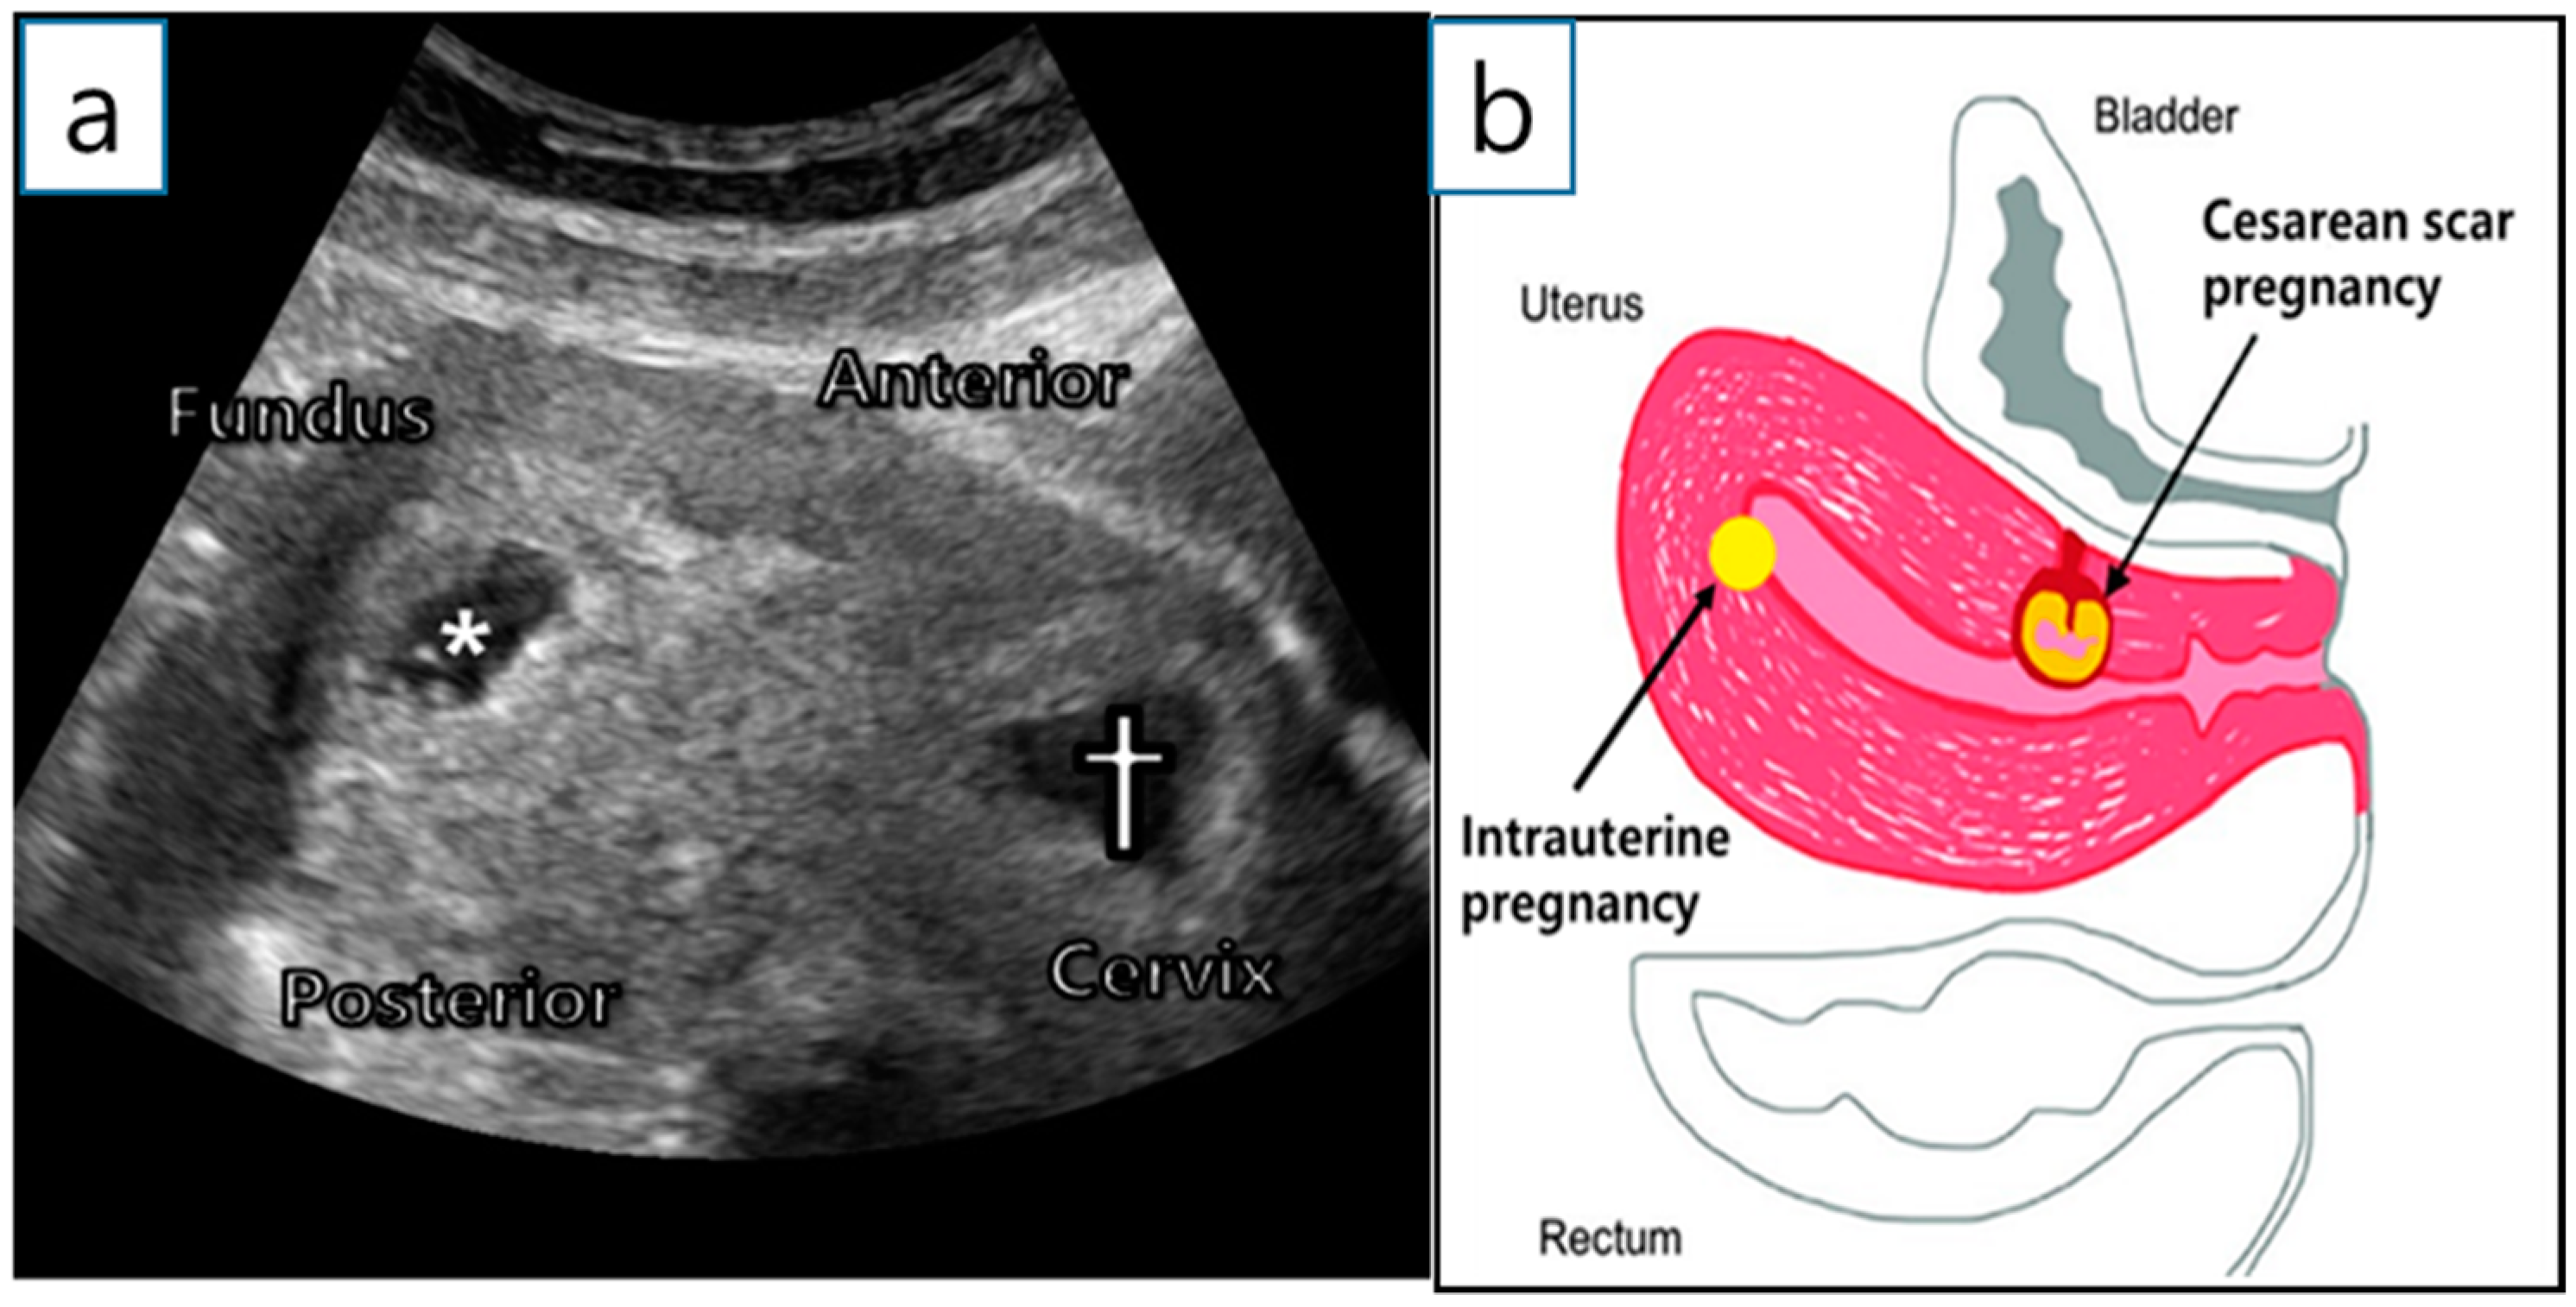

A 36-year-old woman (gravida 2, para 1) was transferred from a local hospital because of a cesarean ectopic pregnancy with IUP. The patient underwent in vitro fertilization-embryo transfer (IVF-ET) using two ova. Two years ago, she delivered a baby via a lower segment cesarean section. Ultrasonography at 6+1 gestational weeks (GW) revealed two gestational sacs; one in the uterine fundus and the other in the anterior uterine isthmus (Figure 1a,b). Both had fetal cardiac activity, and the mother had no vaginal bleeding or abdominal pain.

Figure 1. Initial examination. (a) Initial transvaginal ultrasound examination at 6+1 GW. *—intrauterine gestational sac; †—CSP. (b) Description of sagittal plane.